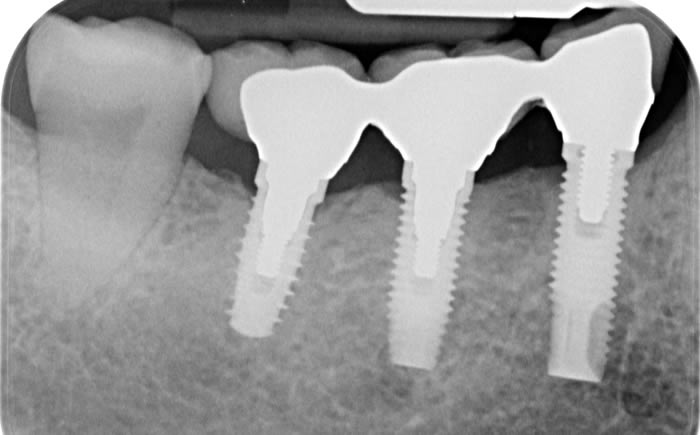

Back teeth replaced by dental implants

Case One (3 images)

Missing lower teeth replaced by three dental implants and crowns.

Case Two (5 images)

Six missing lower back teeth replaced by dental implants